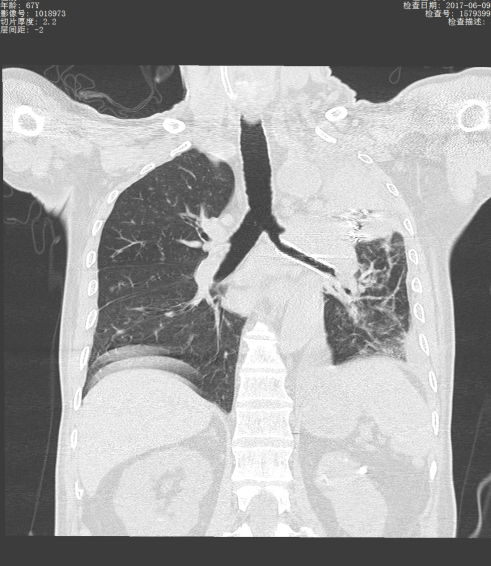

近年来,贵州航天医院各科室紧跟医学前沿,不断强技术、补短板,大力开展新技术、新项目,完成了许多高精尖、高难度、本地区“首例”的技术,填补了医院医疗技术空白,满足了群众日益增长的医疗需求。 贵州航天医院呼吸与危重症医学科是贵州省内呼吸疾病治疗规模最大,诊疗项目最全的呼吸疾病品牌科室,呼吸介入技术达到了全国先进水平,在贵州省内处于领先的地位。 本期,我们将为大家带来呼吸与危重症医学科特色技术——气道支架置入技术治疗呼吸不畅(已纳入乙类医保报销)。 案例分享 一患者因出现呼吸困难、气急等症状,听说我院呼吸与危重症医学科呼吸系统疾病诊疗实力在省内属于前列,慕名前来就诊,入院后,呼吸与危重症医学科为患者完善了胸部CT检查,提示:左主支气管肿瘤生长至气管下段,左肺不张,对此,科室立即组织多学科(MDT)讨论,对患者进行全面的诊断评估,诊断为:左肺鳞癌,左肺不张,气管下段内生型狭窄,左主支气管堵塞。 在充分了解患者及家属的治疗需求和征得治疗同意后,为进一步减轻患者呼吸困难症状,决定为患者实施气道支架置入技术,通过将支气管镜插入到气管中,使用气道球囊扩张器对狭窄的气道进行扩张,在病变部位置入支架扩张狭窄的支气管后,患者安全返回病房。 国产镍钛记忆合金支架植入步骤 术后,患者左主支气管通畅。 什么是气道支架置入技术 气道支架置入技术是一种用于治疗气道狭窄及气道相关性瘘等疾病重要的手段,尤其适用于因恶性肿瘤或其他原因导致的呼吸困难患者。是利用一种保持管腔完整性的人造装置——支架并应用支架置入器在X线透视或支气管镜直视下将支架置入气道保持气道通气功能的一种方法。 目前气道支架最常见的类型有可膨胀金属气道支架、硅酮支架及混合性支架等,以可膨胀金属支架为最常用。 气道支架置入技术原理 是将具有一定张力和弹力的支撑物(即气管支架)置入气道内,将狭窄或塌陷的气道撑开,从而维持气道通畅,或堵住破裂的瘘口。根据气管、支气管不同部位的解剖特点和病变情况,选择对应型号的支架,并通过气管镜的指引,在病灶位置植入合适的支架,也可根据气道的收缩性、不规则性和狭窄程度,进行适当调整。 气道支架置入技术优势 (一)快速缓解呼吸困难:支架置入能够迅速撑开狭窄或塌陷的气道,显著改善患者的呼吸困难症状。 (二)降低气道塌陷风险:对于某些肿瘤或炎症引起的气道狭窄,支架置入可以稳定气道结构,降低气道塌陷和窒息的风险。 (三)创伤小、恢复快:相较于传统手术,气道支架置入术具有微创的特点,患者术后恢复较快,痛苦较小。 气道支架可减轻或抵抗外部压力,扩大狭窄气道后,中央气道梗阻的症状和体征可立即减轻或消除,肺功能、运动能力及生活质量也得到改善。理想的气道支架应具备对气道壁物理性刺激小、置入后不移位、能阻止肿瘤或组织向支架内生长、不影响排痰、可以并容易回收等特点。 贵州航天医院 呼吸与危重症医学科专家团队 廖江荣 国务院政府特殊津贴专家 二级教授 主任医师 贵州航天医院副院长 国家级学术任职: 第二届中国医药教育协会介入微创专业委员会呼吸分会副主任委员 中国抗癌协会肿瘤微创治疗专业委员会常务委员 中国防痨协会结核病转化医学专业分会常务委员 第一届中国人体健康科技促进会呼吸介入专委会常务委员 中国医疗保健国际交流促进会结核病学分会第三届委员会常务委员 中国抗癌协会肿瘤微创治疗专业委员会粒子治疗学组第四届委员会委员 中华医学会结核临床专业委员会内镜介入委员 中华医学会放射学分会第十五届委员会介入学组呼吸系统介入专业委员会委员 北京健康促进会中青年专家委员会胸部疾病精准活检分委会副主任委员 中国医师协会介入医师分会第二届委员会肿瘤消融专业委员会委员 中国结核病防治综合质量控制专家指导委员会委员 亚洲冷冻治疗学会常务委员 世界内镜医师协会呼吸内镜协会常务理事 内镜临床诊疗质量评价专家委员会委员 “西部呼吸介入联盟”副理事长 专业擅长: 呼吸系统(肺)疑难病的诊断及危重病的抢救,呼吸系统(肺)感染性、疑难性疾病介入快速诊断(ROSE),尤其在肺癌、肺小结节早期诊断,肺癌微创综合靶向治疗,难治性、复治性、重症肺结核诊疗,硬质支气管下复杂性气道狭窄诊治,纤支镜介入治疗气道肿瘤、结核、气道狭窄(球囊扩张、支架植入、高频电刀、氩气刀、冷冻、灌洗、注药、微波消融),间质性肺疾病的诊疗上具有极高水平;带领团队勇于创新,在贵州省率先开展多项新技术、新疗法,如CT引导下及纤支镜下I125粒子植入及CT引导下微波、射频消融介入治疗肺癌等多项新技术,带动了贵州省肺部疾病的介入治疗水平提高。 蒋 婷 呼吸与危重症医学科 总负责人 副主任医师 专业擅长:从医20余年,在呼吸系统疾病、介入呼吸病学、肺部结核、肺部肿瘤等方面具有丰富的临床经验和专业技能,尤其是慢性阻塞性肺疾病、支气管扩张、肺结核、耐药肺结核、肺癌、胸腔积液等肺部疾病的诊治、微创介入、危重病患者抢救。 现任中国防痨协会人兽共患结核病专业分会委员,中国女医师协会第一届介入专业委员会委员,贵州省基层呼吸疾病防治联盟-间质性肺疾病联盟委员,贵州省防痨协会第七届理事会理事,贵州省中西医结合学会呼吸专业委员介入呼吸病学组委员,贵州省遵义市中医药学会中西医结合肺病(呼吸)分会副主任委员,贵州省遵义市中医药学会中医肿瘤专业委员会常委;发表论文数篇,参与并主持多项科研项目。 李桂凤 呼吸与危重症医学科 三病区 主任 副主任医师 专业擅长:从事呼吸系统疾病、结核病学、介入呼吸病学、肿瘤综合治疗、呼吸康复等临床工作20余年,擅长呼吸内科常见病、多发病及疑难重症危重病症的诊治,尤其对重症疑难结核及耐药结核病、介入治疗(肺)呼吸系统疾病、呼吸危重病抢救等方面具有较高诊疗水平。 中国防痨协会非结核病专业委员会委员,贵州省中西医结合学会第六届呼吸专业委员会委员,贵州省康复学会睡眠障碍康复专业委员会委员,遵义市呼吸内科医疗质量控制中心委员,遵义市落实民生实事结核病筛查阅片专家组成员;主持及参与实用新型专利3项。 周裕祥 呼吸与危重症医学科 四病区 主任 副主任医师 专业擅长:经皮肺介入、经血管介入诊疗技术。 贵州省中西医结合学会呼吸专业委员会介入呼吸病学组常务委员,中国医师协会呼吸医师分会介入呼吸病学工作委员会呼吸病血管介入学组委员,贵州省中西医结合学会呼吸学分会委员,遵义市医学会放射肿瘤治疗学分会委员,中国医药教育协会介入微创呼吸分会委员,北京健康促进会中青年专家委员会胸部疾病精准活检分委会委员;曾赴重庆医科大学RICU、珠海市人民医院介入科进修学习。 杨 芳 呼吸与危重症医学科 内镜中心 主任 副主任医师 专业擅长:从事临床工作约16年,对呼吸危重病的救治有独到的见解,尤其擅长呼吸系统疾病的介入诊疗,对呼吸内镜下的诊治及经皮肺穿刺诊疗技术具有丰富的临床经验。 亚洲冷冻治疗学会委员,中国医药教育协会介入微创呼吸分会委员,西南结核病医院联盟第二届委员会秘书/委员,贵州省中西医结合学会第六届呼吸科专业委员会委员,贵州省中西医结合学会呼吸专业委员会介入呼吸病学组秘书,贵州省中西医结合学会呼吸专业委员会基层康复学组副组长,贵州水利电力医学科学技术会高原医学分会委员,遵义市中医院学会中西医结合肺病(呼吸)分会秘书/常务委员,遵义市医学会肿瘤学分会(第二届)委员,遵义市医学会放射肿瘤治疗学分会第二届委员;主持及参与科研课题多项,参编著作《呼吸内镜操作技术规范》、《介入结核病学》,发表论文数篇。 贵州航天医院 呼吸与危重症医学科专家团队 贵州航天医院呼吸与危重症医学科以呼吸危重症和介入呼吸病学为强力推手,以肺部感染性疾病及肺癌、肺小结节的早期精准诊疗、慢性呼吸疾病康复治疗为特色,以人才团队建设为核心的科室发展模式,现已成为省内呼吸疾病治疗规模最大,诊疗项目最全的呼吸疾病品牌科室。是贵州省医学重点学科、临床医学重点专科建设单位,遵义市首批呼吸重点学科、重点专科建设单位。是国家卫健委能力建设和继续教育肿瘤微创介入建设中心、贵州省县级医院微创介入培训中心、遵义市呼吸疾病临床医学中心。是国家呼吸医疗质量控制与管理哨点医院、遵义市呼吸内科专业医疗质量控制中心。是中国医药教育协会介入微创呼吸分会呼吸介入技术培训中心单位;国家卫健委海医会呼吸分会ROSE专委会“诊断性介入肺脏病学快速现场评价”培训基地;中国肺癌防治联盟“贵州航天医院肺结节诊治”分中心,中国人体健康科技促进会呼吸介入技术培训基地,贵州省中西医结合会呼吸学分会呼吸介入专委会主委单位。 基本情况 平均每年开展气管镜诊疗约4000例,经皮肺穿刺介入诊疗近千例,开展的项目包括经支气管镜(软、硬)下冷冻、氩气刀、高频电刀、球囊扩张、支架置入、超声内镜诊疗等气道介入诊疗技术,经皮肺穿刺活检及肿瘤消融术(微波、冷冻)、ROSE技术、内科胸腔镜诊疗及经血管介入诊疗技术,且多项呼吸介入诊疗技术在省内处于领先水平。 诊疗范围 致力于呼吸系统感染性、疑难性疾病的介入快速精准诊疗;肺癌与肺小结节早期精准诊疗水平项目提升。擅长于呼吸系统(肺)疑难病的诊断及危重病的救治,尤其在肺癌、肺小结节的早期诊断;肺癌综合靶向治疗;肺结核综合诊疗;肺部疾病的介入诊疗在省内处于前沿水平。